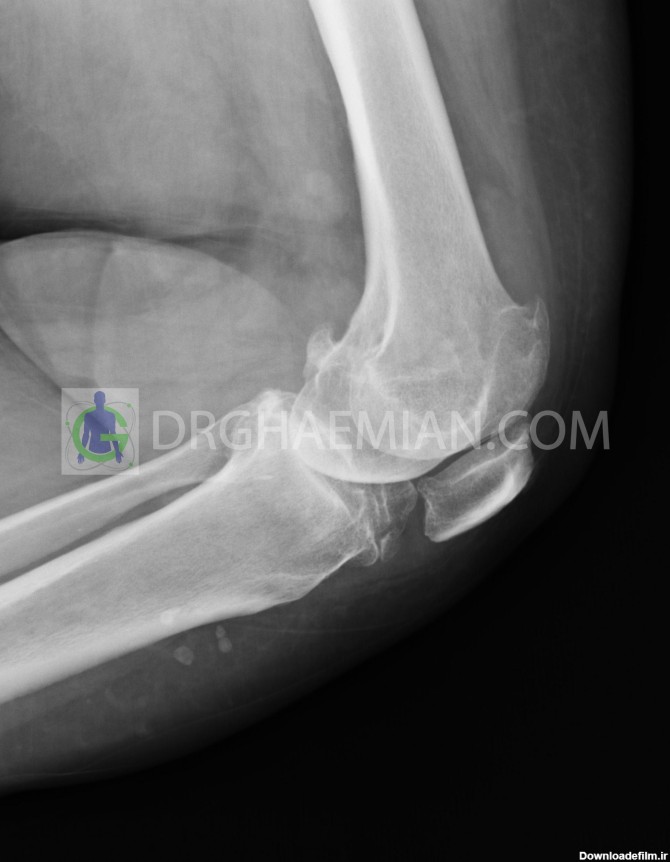

عکس رادیولوژی آرنج سالم کودک

رادیولوژی استخوان بازو باید در دو نمای قدامی-خلفی و جانبی انجام شود و مفاصل شانه و آرنج را نیز در بر می گیرد.عکس رادیولوژی مفصل آرنج شامل..